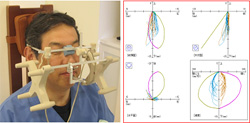

当院では4.0倍~5.0倍の拡大スコープを着けて診療しております。 |

顎機能検査装置 |

シロナソアナライジングシステム |